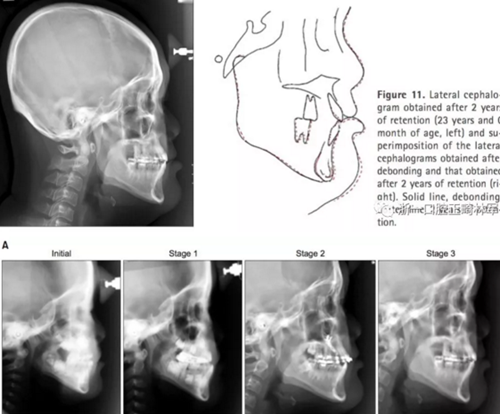

2年后隨訪提示治療結(jié)果得到保持(圖10,11,表1-3),不同階段的頭側(cè)重疊結(jié)果見圖12。

總療程為15年10個(gè)月。達(dá)到尖牙I類及磨牙II類關(guān)系建立正常的覆合覆蓋。盡管后縮的上頜由于長期面弓治療有顯著改善,但由于持續(xù)的下頜骨發(fā)育,患者表現(xiàn)出III類面型。因此建議手術(shù)后移頦部,但病人和他的父母拒絕手術(shù)。

頭側(cè)結(jié)果顯示上頜輕度后縮(SNA 79.1°; A to N,-5.0mm;A到VRP水平距離為57.5mm),下頜輕度前突(SNB,80.2°,Pog-N-7.2mm;POG到VRP水平距離,57.4mm),低角ANB(-1.1°),正常下頜平面角(FMA,29.5°),正常下頜角(119.8°),上頜切牙斜度正常(U2 to SN,106.7°)和下頜切牙的舌傾角(IMPA,85.0°)。正常的覆合和覆蓋(覆合,1.7mm,覆蓋,1.9mm)(圖8和9,表3)。